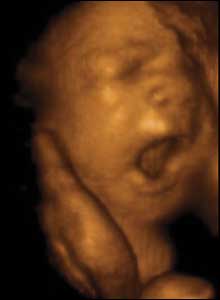

28 týdnů, 29 cm

Děti mohou zívat od začátku 12. týdne. Možná je to přirozený způsob, jak zajistit, aby se novorozenec mohl poprvé na světě nadechnout.